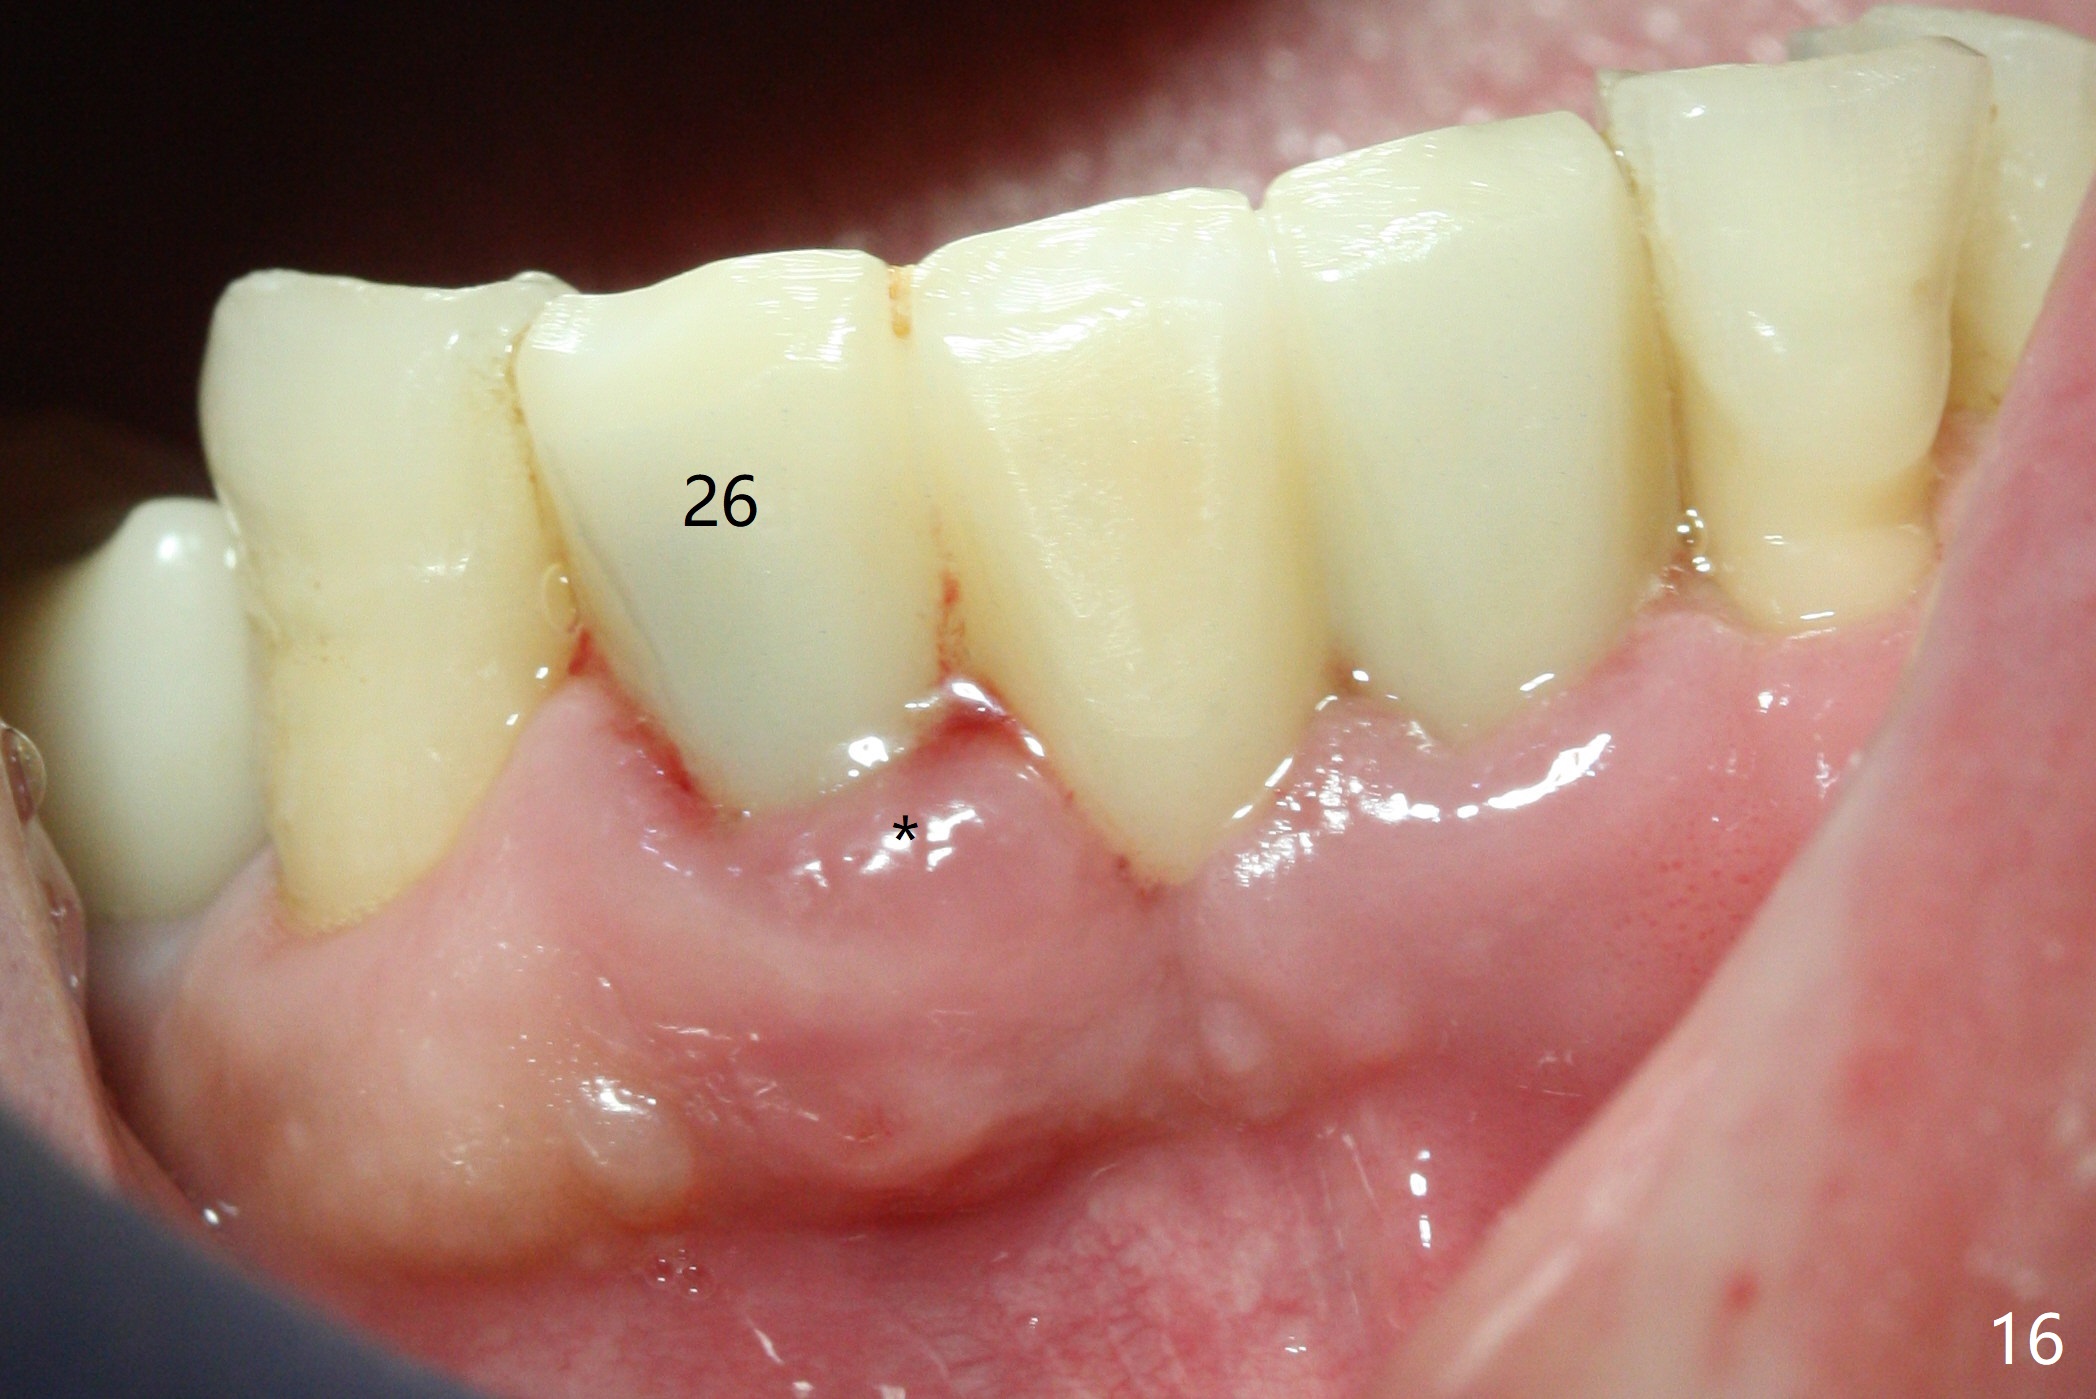

The infection persists at #26 four years 8 months post cementation (Fig.16 *). CBCT is taken. In fact the implant at #26 was placed lingual (Fig.17), while that at #24 buccal (Fig.20). The 2nd option is to remove the implant at #26 and place a 2 mm one at #25 (Fig.18,19). Fabricate a 3-unit cantilever FPD. Take 5x5 cm CT with 1.2 mm drill in place for 10 mm. Change the trajectory and position if necessary.